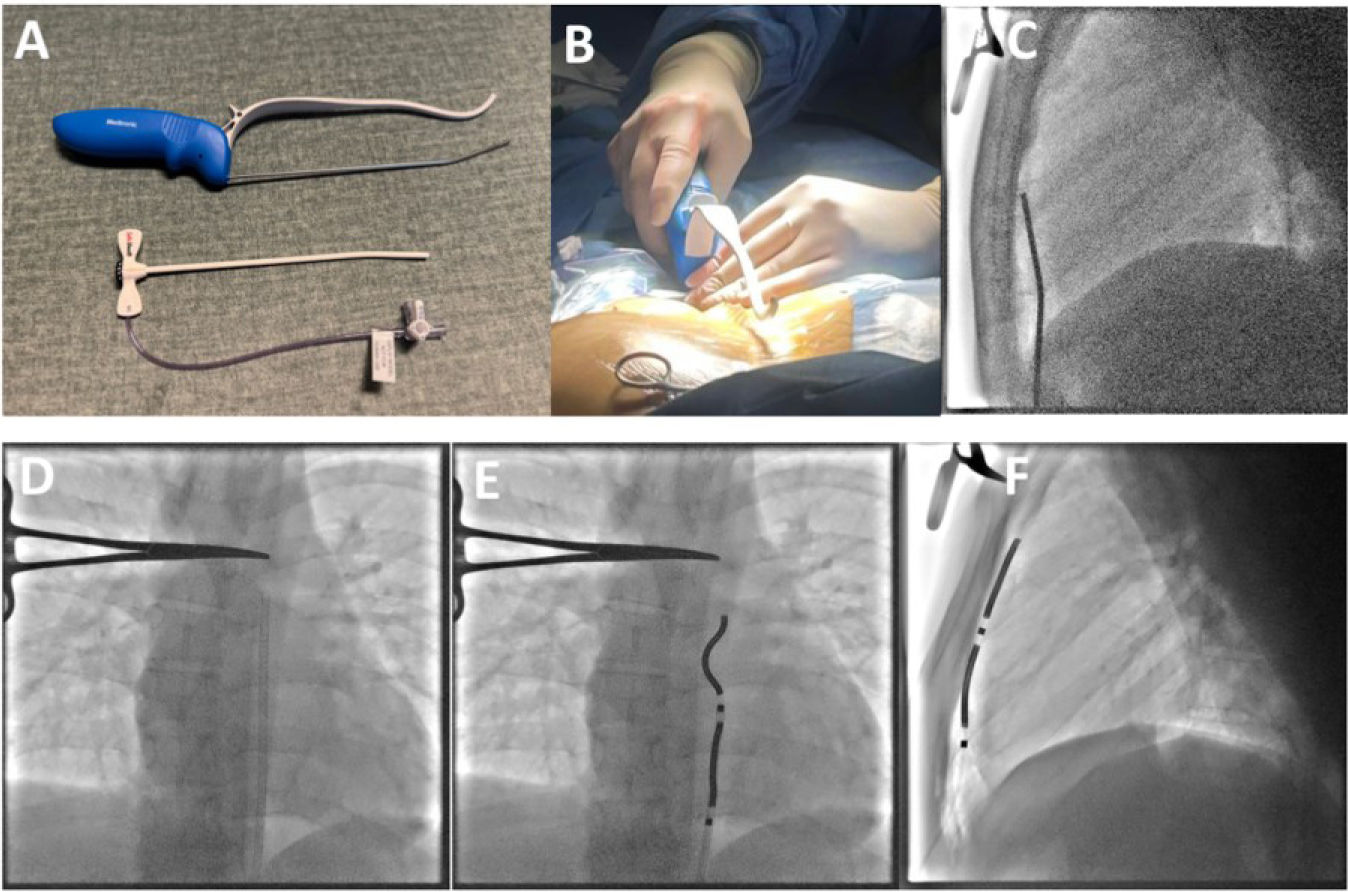

The implantation technique followed the manufacturer's recommended procedure.6 A subxiphoid horizontal 2 cm incision was made to access the retrosternal space using blunt dissection. The lead delivery sheath was advanced into the anterior mediastinum along the posterior sternum, under anteroposterior and lateral fluoroscopic guidance (Figure 1). The dedicated substernal lead was then tunnelled and positioned to maximize R-wave sensing and shock vector efficacy. The generator was implanted subcutaneously in the left mid axillary region, below the level of the maximal dimension of the heart, as assessed in the anteroposterior fluoroscopic view. Lead connection and system integrity testing were performed before wound closure. Hemostasis was ensured and wounds were closed in multiple layers.

Positioning of the dedicated substernal lead during one of the implant procedures. (A) Dedicated sternal tunneling tool; (B) positioning of the tunneling tool in the incision site; (C) the tunneling rod was advanced under fluoroscopic guidance; (D) the lead delivery sheath was positioned in the anterior mediastinum along the posterior sternum; (E) the lead was then tunneled and positioned to maximize R-wave sensing and shock vector efficacy; (F) the final lead position was in close proximity with the posterior sternum.